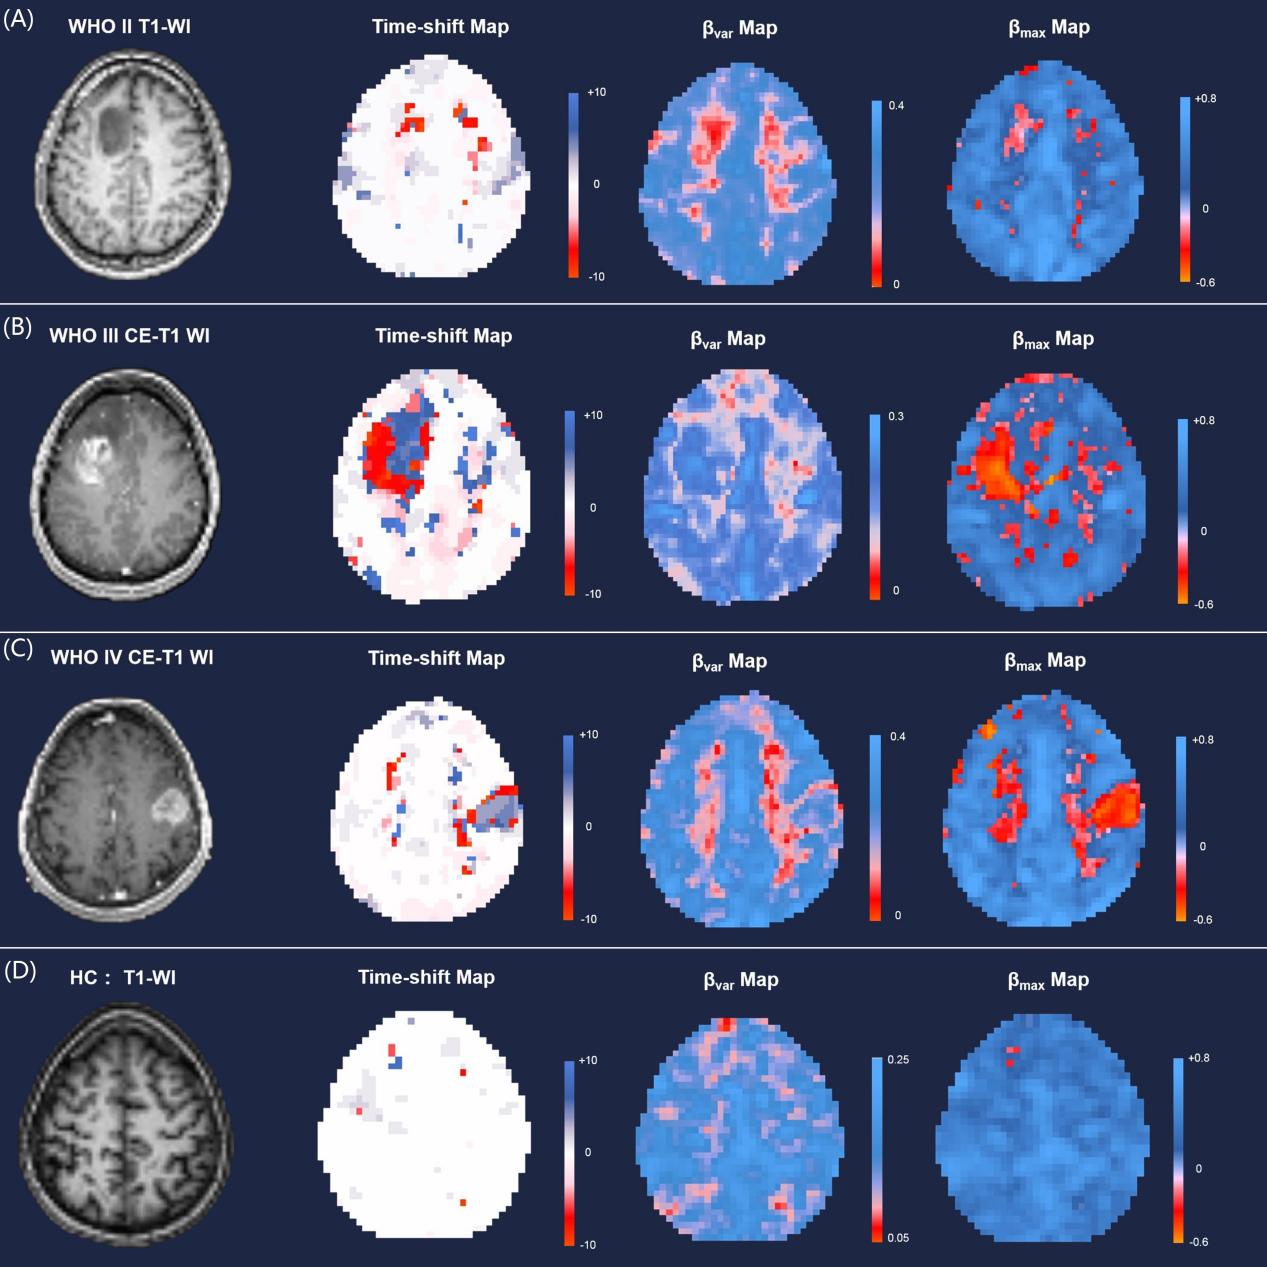

研究团队基于BOLD fMRI数据,通过对系统性低频振荡成分的时间偏移分析(time shift analysis,TSA),在不引入外源性药物对比剂的情况下对全脑血管的功能进行了定量评估。研究发现,胶质瘤及周边水肿区域的血管功能失调主要表现为同步性显著降低,且高度恶性胶质瘤的肿瘤血管发展了具有自主拮抗趋势的动力学模式。肿瘤对侧大脑半球的血管同步性显著增强,并与胶质瘤的生物侵袭性密切相关。基于肿瘤和血管失调的特征,联合决策树模型,该研究工作实现了个体水平的胶质瘤恶性度的准确预测(WHO II/III/IV级同时分类,准确率达90.91%)。上述结果证实胶质瘤在全脑水平触发了血管网络的功能重塑,为深入理解胶质瘤的疾病机理提供了新的参考依据。

胶质瘤患者和健康对照者BOLD-fMRI时间偏移分析示例。A.WHO II胶质瘤患者(35岁,男性,左额星形细胞瘤); B. WHO III胶质瘤患者(26岁,女性,左额间变型星形细胞瘤); C. WHO IV胶质瘤患者(68岁,女性,右额胶质母细胞瘤); D. 健康被试(HC, 26岁,女性)。